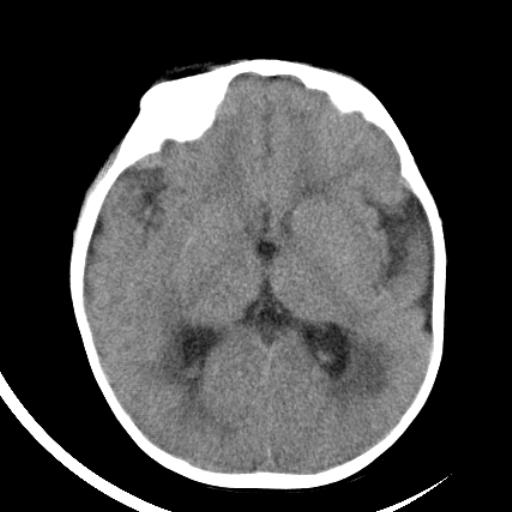

双侧脑室前后角周围白质片状低密度影,双侧侧脑室旁、双顶叶皮层及皮层下多个小原点状钙化灶,不除外torch感染。右顶叶脑回似乎较对侧大,建议mri检查以除外脑发育异常。

考虑:1、巨脑回畸形(皮质明显增厚+脑回明显增宽+白质减少)。

2、torch综合征(室管膜下钙化+白质内及皮髓质交界处多发钙化)。

1、巨脑回畸形(皮质明显增厚+脑回明显增宽+白质减少)。